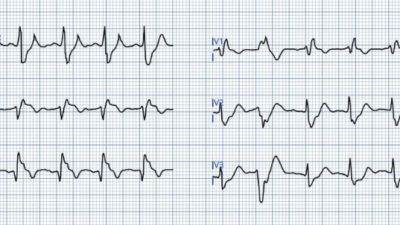

Figure-2: ECG Findings associated with acute PE.